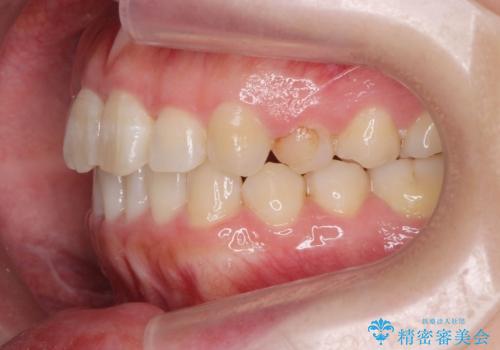

- 前歯のねじれを改善したい、と矯正治療を希望され来院されました。

上下の歯のがたつきを改善するマウスピース矯正治療と、下顎に見られる大きな骨隆起を外科的に除去する治療計画を進めていきます。

歯並びが改善したとともに、骨隆起を除去したことで舌をしまうスペースも増え安定した口腔内環境を確立することができました。